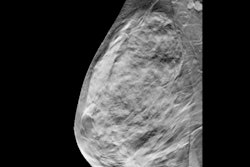

Digital tomosynthesis generates image slices from low-dose projections at different angles, the team explained; it has been established as an effective technique in breast imaging and has begun to be explored for use in orthopedic surgery and musculoskeletal applications. X-ray tomosynthesis may be a "suitable alternative to multidetector [CT] of the appendicular skeleton for trauma or preoperative imaging," eliminating the problem of superimposition of anatomical structures in spinal x-ray imaging, the group wrote.

The team conducted a study that included eight cadavers and used a gantry-free twin robotic scanner to procure lateral conventional x-rays and x-ray tomosynthesis images of the lumbar spine. Five musculoskeletal radiologists assessed image quality between the two techniques, including the extent of any image quality deterioration near scan volume margins.

The study showed that x-ray tomosynthesis offered substantial dose reduction compared to conventional x-ray. Diagnostic image quality was highest using a 30 fps (frames per second) wide-angle tomosynthesis protocol. The team also reported good-to-excellent interrater reliability on x-ray tomosynthesis imaging (range, 0.85 to 0.95, with 1 as reference).